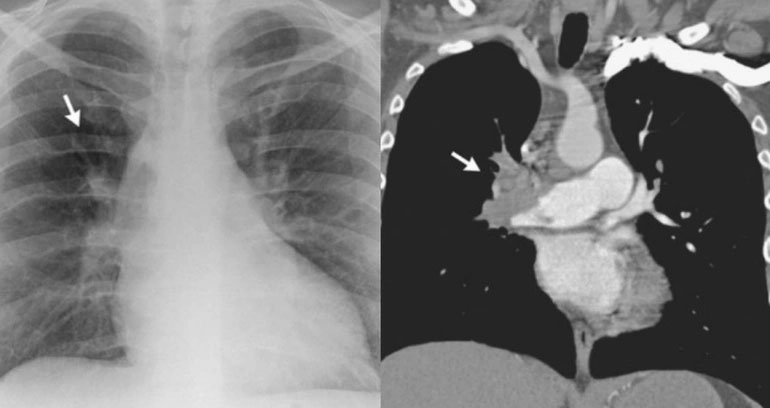

"Chúng tôi nghi ngờ bệnh nhân có huyết khối ở phổi nên chỉ định chụp CT. Kết quả cho thấy huyết khối hoàn toàn động mạch phổi phải. Ngay sau đó, bệnh nhân đã được điều trị bằng thuốc tiêu sợi huyết thành công", BS Hiếu cho biết.

Trường hợp trên may mắn nhờ chẩn đoán kịp thời nên đã thoát chết trong gang tấc. Hiện sức khỏe bệnh nhân ổn định. Với những người bị huyết khối phổi nếu không được phát hiện sớm và xử trí kịp thời, cục máu đông có thể gây hoại tử mô phổi dẫn đến suy hô hấp và tử vong.